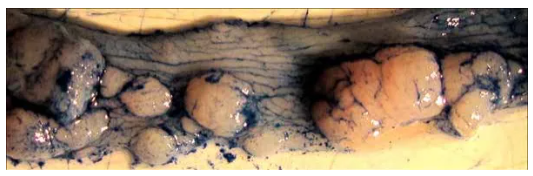

3. 處死后取小鼠結(jié)腸,可觀察形成的腫瘤。值得注意的是,末端結(jié)腸/直腸腫瘤負(fù)荷較高(左上圖),近端結(jié)腸腫瘤呈現(xiàn)褶皺狀紋理(右上圖),腫

瘤負(fù)荷很少。近距離觀察末端結(jié)腸可觀察到許多不同大小的腫瘤(下圖)。